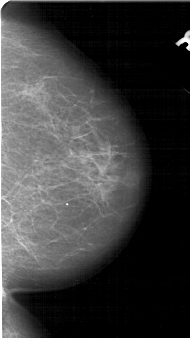

A_1651_1.LEFT_MLO

LEFT_MLO LINES 5491 PIXELS_PER_LINE 2911 BITS_PER_PIXEL 12 RESOLUTION 43.5 OVERLAY